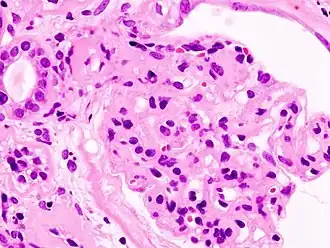

![]() Fotografía microscópica de un glomérulo lesionado consecuencia de una nefropatía diabética, la principal causa del síndrome nefrótico en adultos. | ||

El síndrome nefrótico (SN) es un trastorno renal causado por un conjunto de enfermedades, caracterizado por aumento en la permeabilidad de la pared capilar de los glomérulos renales que conlleva a la presencia de niveles altos de proteína en la orina (proteinuria) mayor a 3.5 g por día, niveles bajos de proteína en la sangre (hipoproteinemia o hipoalbuminemia), ascitis y en algunos casos, edema, colesterol alto (hiperlipidemia o hiperlipemia) y una predisposición para la coagulación.

El motivo es una lesión del glomérulo renal, ya sea ésta primaria o secundaria, que altera su capacidad para filtrar las sustancias que transporta la sangre. Los daños causados en el paciente serán más o menos graves, pudiendo surgir complicaciones en otros órganos y sistemas. Las enfermedades asociadas con el síndrome nefrótico en general causan disfunción renal crónica. Sin embargo, en función de la afección y del tipo de lesión, estos sujetos presentan un buen pronóstico bajo un tratamiento adecuado.